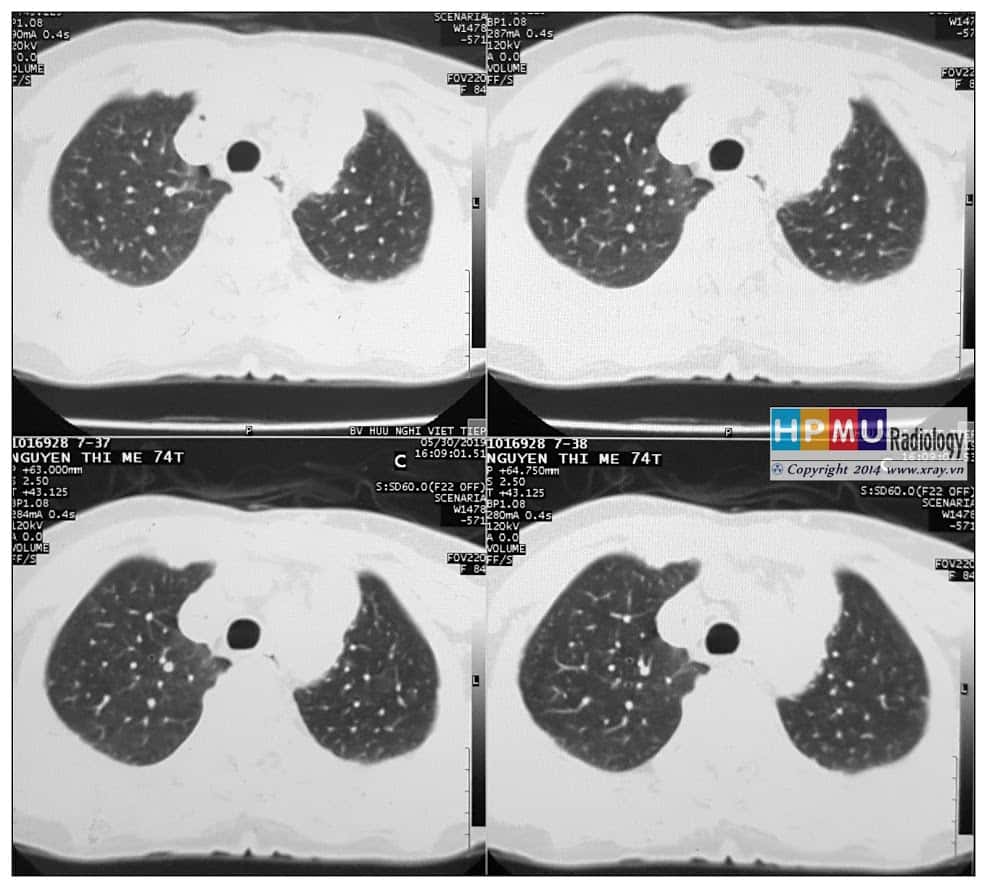

Hạch trung thất

» Thông tin: Nữ giới – 74 tuổi.

» Lâm sàng: Đau ngực.